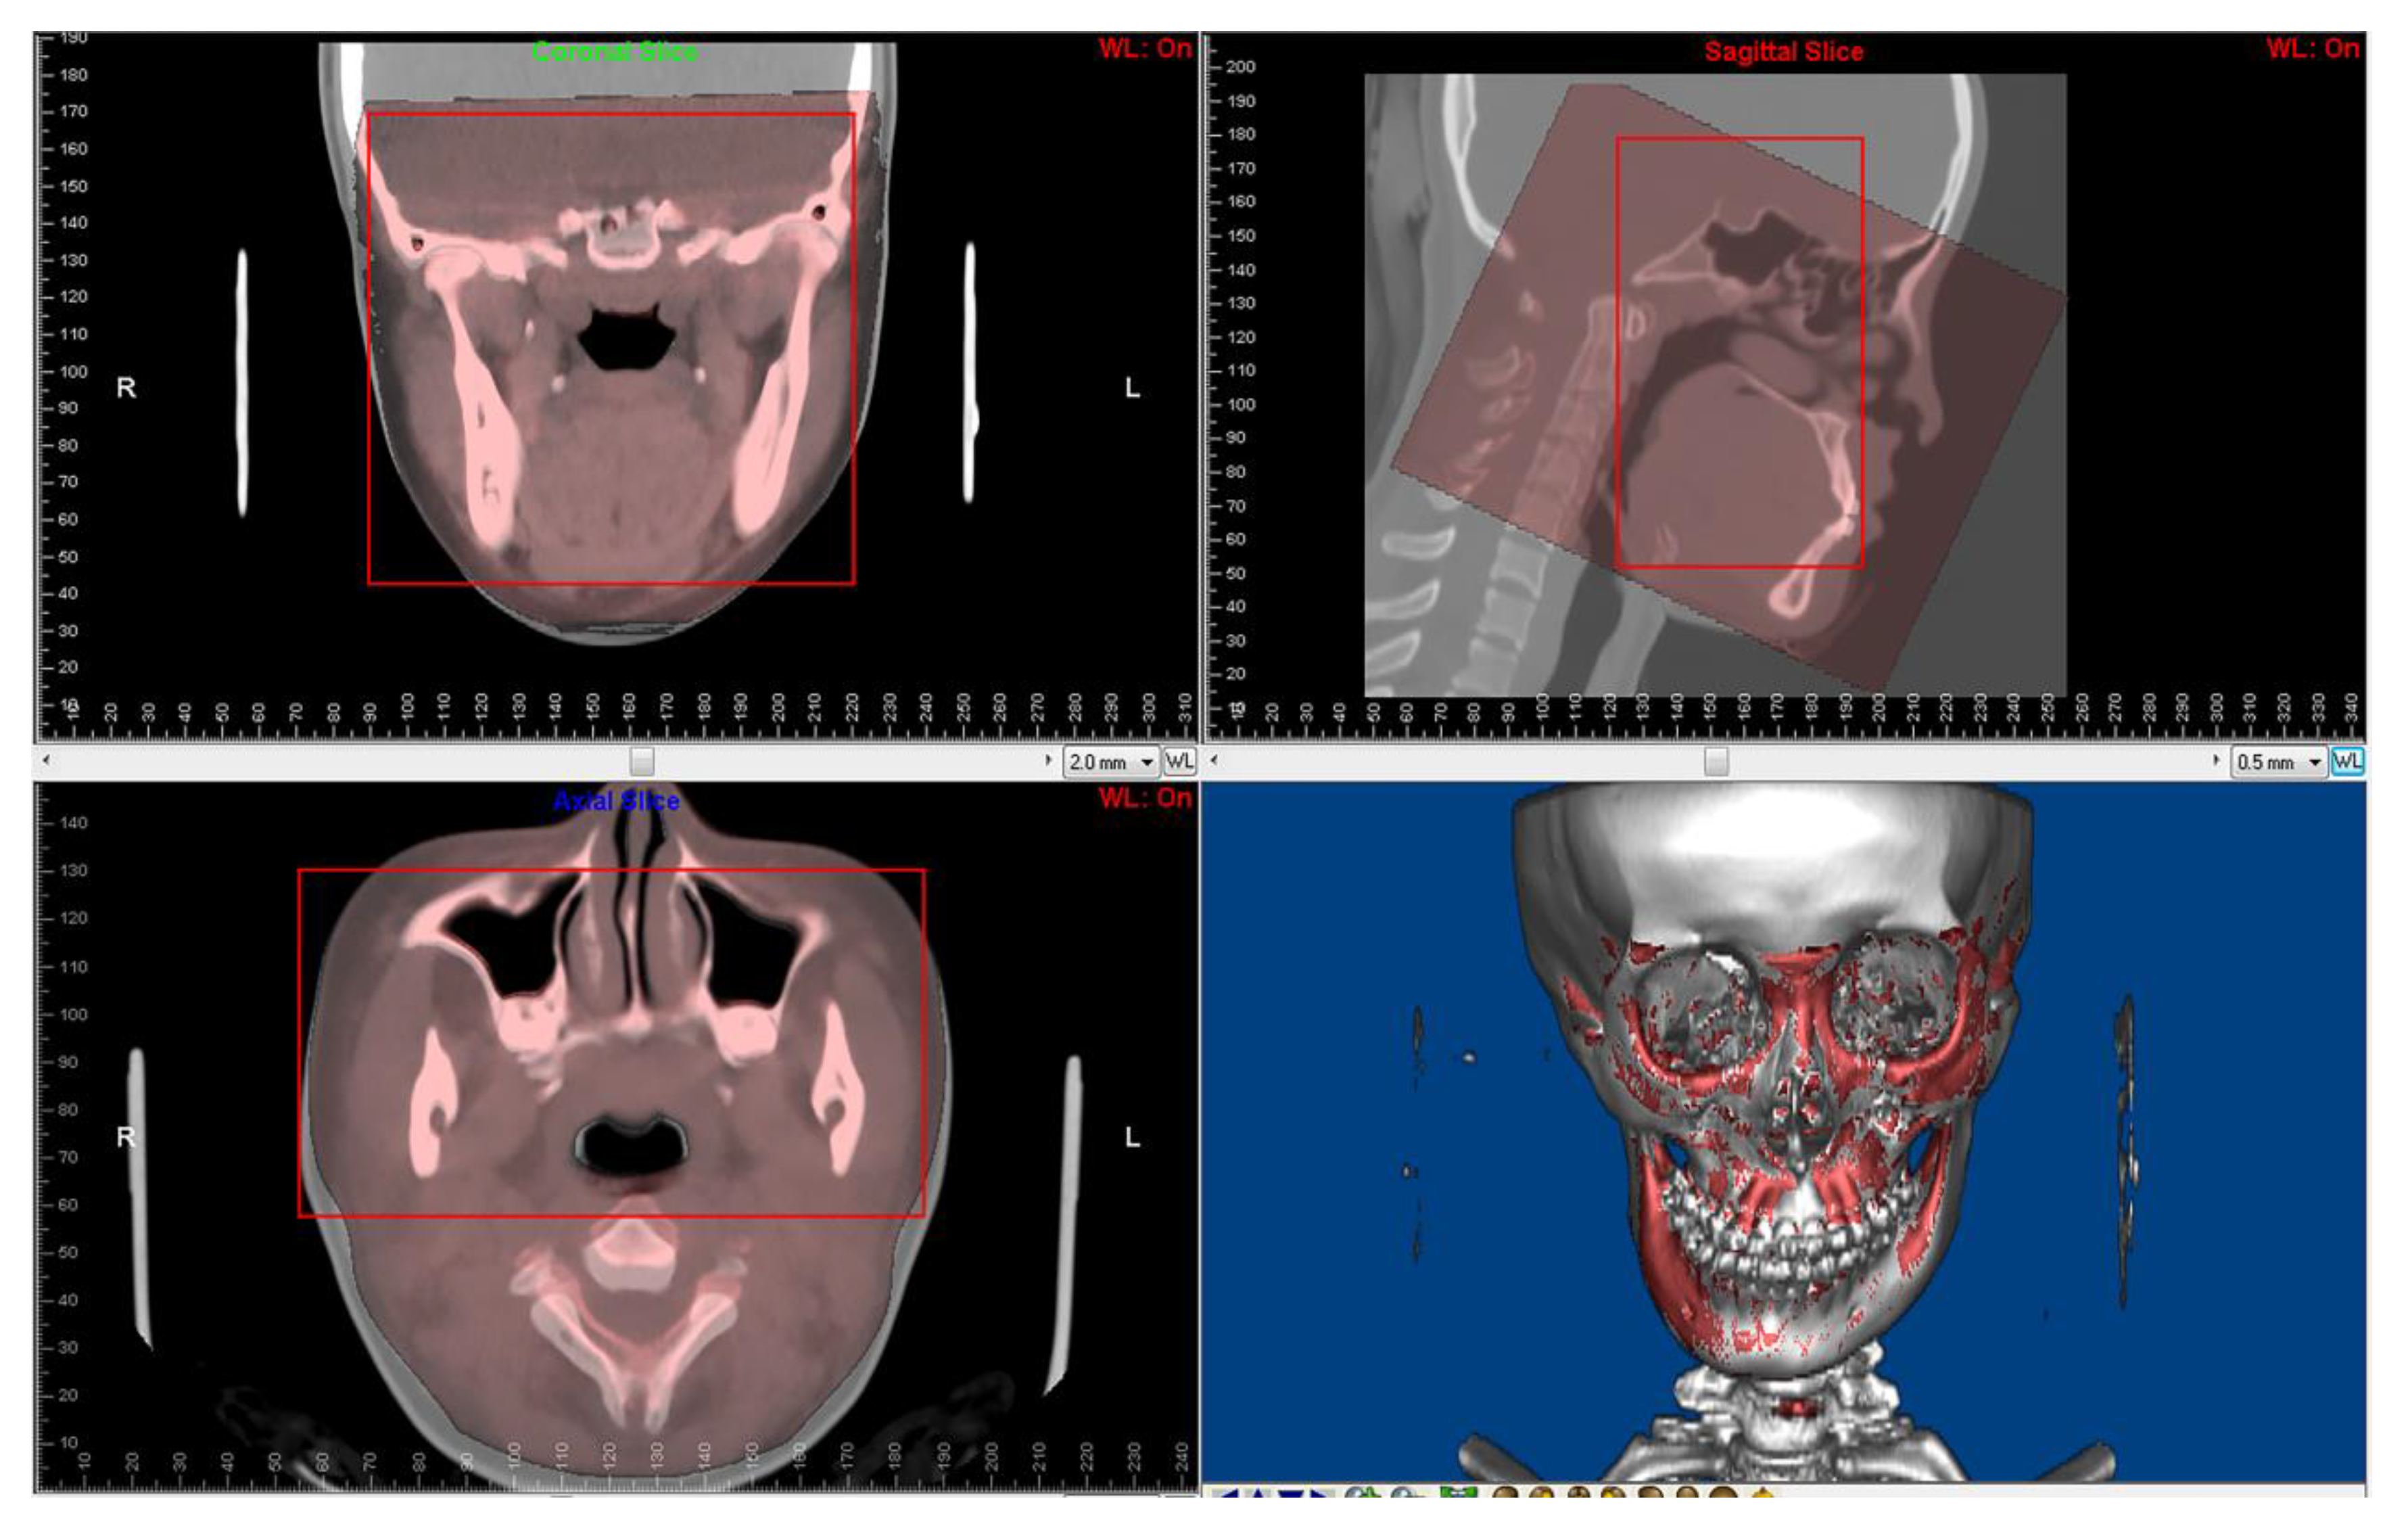

Paired CBCT and CT acquired from the same patients were collected. CBCT was performed for the orthodontic 3D cephalometric analysis and for assessment of alveolar bone thickness and the tooth movement boundary. Due to the incomplete scanning of the cranial base in the CBCT, which is the main reference to determine the position of the maxilla and mandible in orthognathic surgery, spiral CT images were performed presurgically for 3D digital orthognathic surgical planning. The average interval was 2.53 ± 2.23 months. CBCT and CT images were superimposed in Dolphin3D imaging software (version 11.8; Dolphin Imaging and Management Solutions, Chatsworth, CA, USA) (Figure 2) and were exported with orientation.

Figure 2. Superimposition of paired CT and CBCT was performed using Dolphin3D imaging software. The red squares are regions for superimposition.